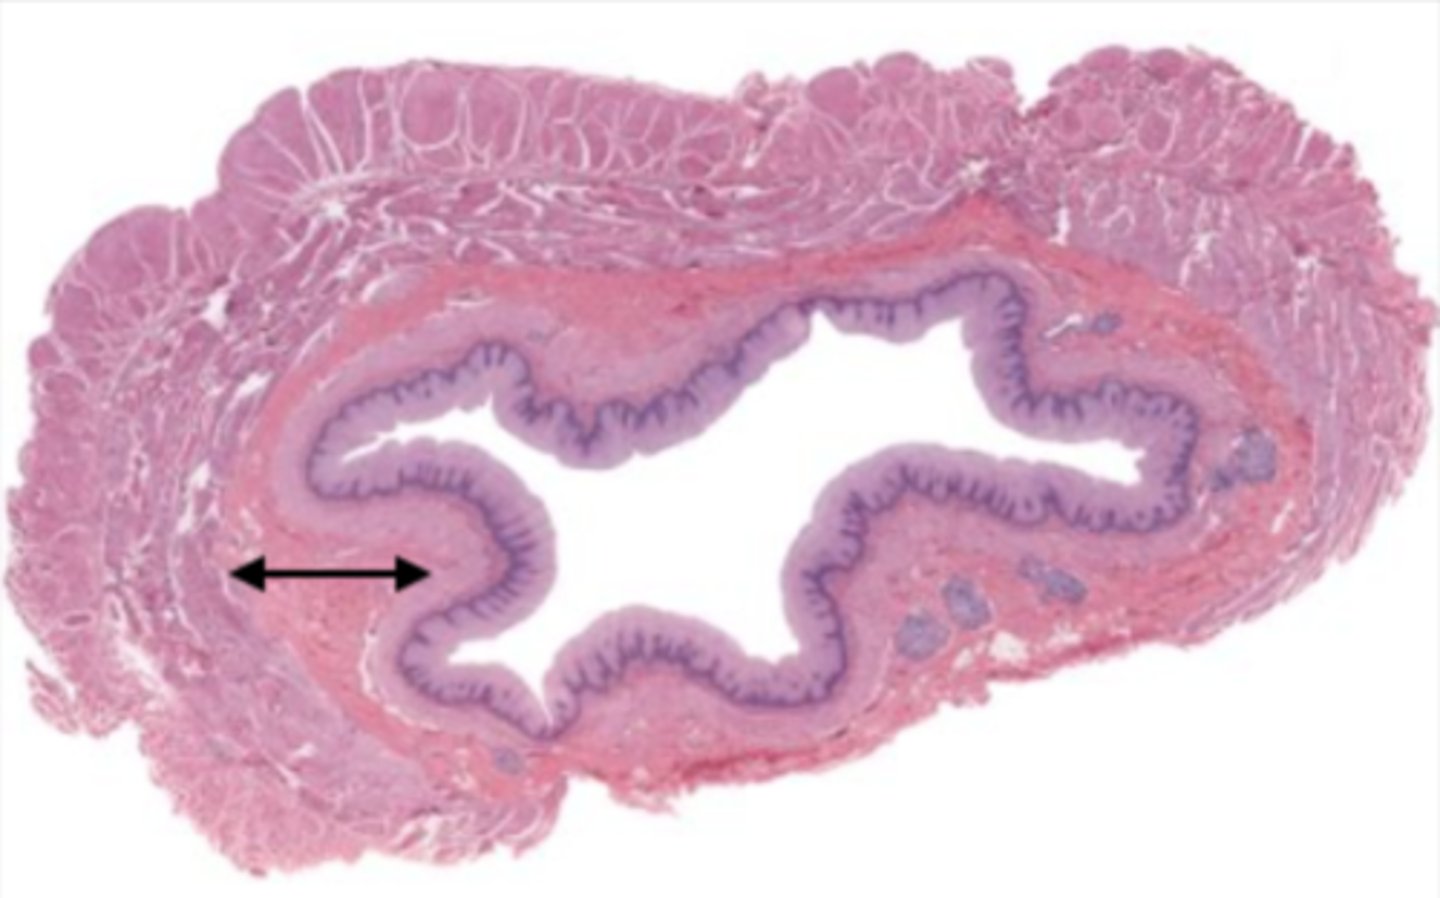

gallbladder (histology)

gallbladder

this tissue's wall structures/layers are different than the rest of the organs

simple columnar epithelium

what kind of epithelium lines the mucosa of the gallbladder

lumen (gallbladder)

mucosa (gallbladder)

mucosal epithelium (gallbladder)

lamina propria (gallbladder)

muscularis mucosa and submucosa

gallbladder tissue does not have _______ and ______

muscularis externa (gallbladder)

serosa/adventitia (gallbladder)